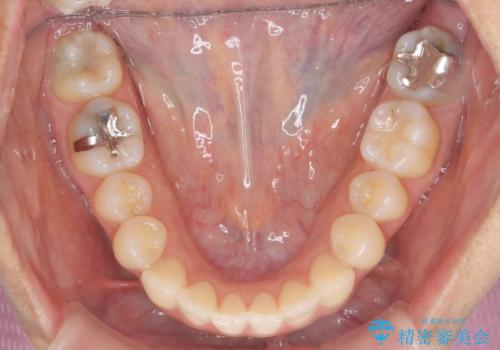

前歯のがたつきをしっかり治すマウスピース矯正

- 前歯のガタガタをきれいに並べたい、と希望され来院されました。

マウスピース矯正インビザラインのクリンチェックを用いて治療前にしっかりと歯並びのゴールのシミュレーションを行い、治療を開始します。

がたつきのないきれいな歯並びに仕上げることができ、満足いただくことができました。